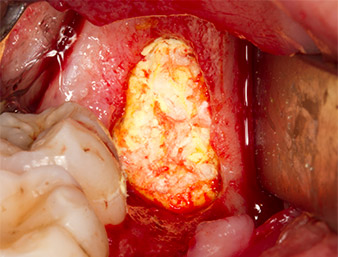

Pour obtenir un matériau autogène en vue du traitement ultérieur de la plaie, des fragments osseux sains sont collectés autour du reste radiculaire à l'aide d’un insert piézochirurgical (Piezomed B5) (Fig. 5).

Piezomed B5

Fig. 5 : Une élévation osseuse est pratiquée dans la région de l’alvéole à l'aide d’un instrument piézochirurgical en forme de burin (Piezomed B5). Cet os est utilisé comme matériau d’augmentation autologue après l’extraction du reste radiculaire (cf. Fig. 13 et 14).

Le tissu autogène est extrait à l’aide de la section en forme de racloir de la pièce active de l’insert et conservé dans un soluté physiologique isotonique jusqu’à utilisation ultérieure (cf. Fig. 13).

Pour exposer le reste radiculaire en minimisant le traumatisme causé aux tissus, un autre insert est utilisé (Piezomed S2) qui est principalement indiqué pour la préparation de la fenêtre latérale dans les élévations de plancher sinusien. La boule diamantée est également utilisée pour adoucir les bords osseux tranchants (Fig. 6 et 7). Tous les inserts Piezomed sont utilisés avec le paramétrage par défaut automatique, et sans la fonction Booster.

Piezomed S2

Fig. 6 : Le reste radiculaire est soigneusement exposé à l’aide d’un insert sphérique diamanté (Piezomed S2), les arêtes osseuses sont adoucies.

Reste radiculaire 38

Fig. 7 : Le reste radiculaire 38 (LL8) est bien exposé dans son alvéole en vue de son extraction ultérieure.